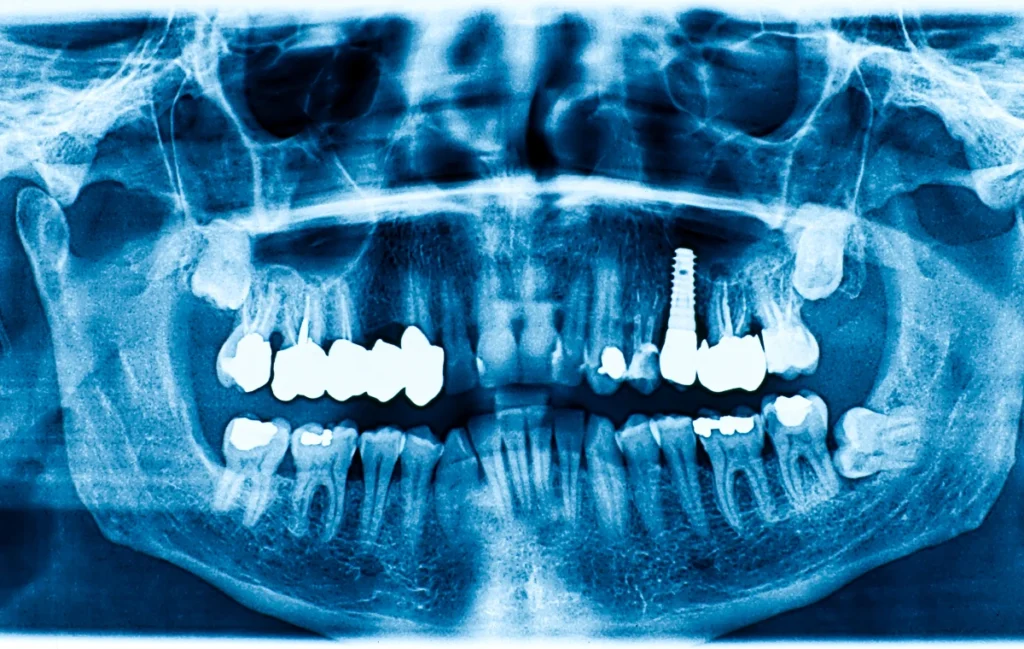

Un implant dentaire est une racine artificielle en titane insérée dans l’os de la mâchoire. Cette base solide supporte ensuite une couronne, un bridge ou une prothèse amovible.

Les consultations préliminaires permettent de vérifier la qualité osseuse. Elles détectent aussi d’éventuelles contre-indications. Si l’os est insuffisant, une greffe peut être envisagée. Grâce à ces analyses, la réussite de l’implantation est optimisée.

Analyse initiale : examen bucco-dentaire et radiographie.

Pose de l’implant : insertion de la racine artificielle dans l’os.

Cicatrisation : l’os s’intègre progressivement autour de l’implant.

Prothèse finale : fixation d’une couronne, d’un bridge ou d’une prothèse adaptée.